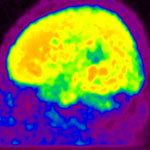

A betegséget először

Alois Alzheimer német ideggyógyász diagnosztizálta 1907-ben. A róla elnevezett kór a gondolkodás és a kognitív funkciók fokozatos elvesztésével jár. Ennek következményeként a beteg magatartása lépcsőzetesen változik, majd demencia és biológiai leépülés következik. Az Alzheimer-kór egy krónikus degeneratív betegség, amely az agy különböző részein (halánték- és homloklebeny, hippokampusz) sorvadást, az idegsejtek degenerációját okozza. A betegség kialakulásának pontos oka egyelőre ismeretlen, de több teória is napvilágot látott már.